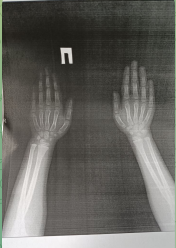

Здравствуйте, доктор! Ребёнку 6 лет вчера сломала ручку. Скажите, на сколько серьёзно повреждение ? Какие возможны рекомендации от Вас? Сейчас запись к травматологу у нас в Академгородке только через неделю практически у всех. Подскажите, что можете и увидили на снимке, пожалуйста!

Спасибо, что ответили. А по снимку можете что то сказать?

Плохо различимо, приносите снимок с собой